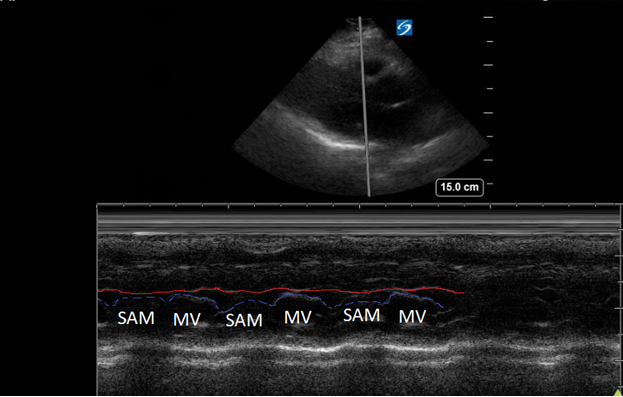

A point-of-care ultrasound was performed to evaluate for potential etiologies of syncope. The ultrasound displayed biventricular and interventricular septal hypertrophy (Figure 2), systolic anterior motion of the mitral valve (SAM, Figure 3), and a “dagger-like” continuous wave Doppler waveform emerging from the left ventricular outflow tract. (LVOT, Figure 4)

Figure 3. Parasternal long-axis view using M-Mode displaying SAM of the mitral valve against the interventricular septum (red line). Note how the mitral valve shifts anteriorly during the same period that the septum contracts posteriorly.

Hypertrophic obstructive cardiomyopathy (HOCM) refers to the common obstructive subset that affects 70% of patients with HCM.6 Left ventricular outflow tract obstruction (LVOTO) has been shown to be an independent predictor for adverse outcomes by multiple studies.7 Traditionally, systolic anterior motion (SAM) of the mitral valve was thought to be pathognomonic for HCM. Recent studies have shown that of the HCM patients with SAM, 25-50% will have LVOTO.8 Using ultrasound, SAM is observed in the parasternal long-axis using M-mode over the anterior leaflet of the mitral valve. The time the valve is contact with the septum quantifies disease severity.